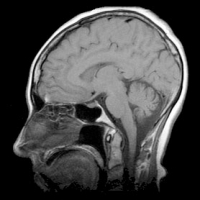

Investigadores del Centro de Salud de la Universidad de Connecticut (UCHC) están explorando aplicaciones de Maple en la interpretación de información de imágenes de resonancia magnética (IRM) para la detección temprana y caracterización de tumores pequeños.

Las redes vasculares necesarias para nutrir el crecimiento en microambientes tumorales pueden ser mucho más densas que en el tejido normal. La densidad vascular es un parámetro importante en la evaluación de la actividad tumoral, pero se reconoce universalmente... |